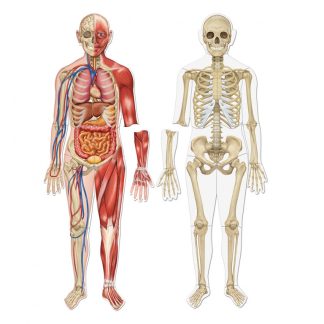

Innehåller 10 bilder som vid vinkling ändras och visar vad som händer i våra största organ i kroppen.

Innehåller bl.a. Hjärtat, Lungorna och hjärnan mm.